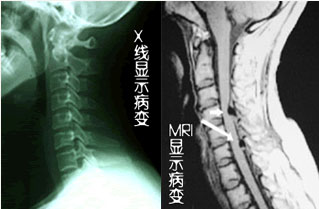

除腰椎外,颈椎部位也是椎管狭窄的高发部位,颈椎管狭窄具体是指颈椎管各个方向径线减小,或者说容积减小。颈椎管狭窄可减少脊髓和神经的有效空间和血供,引起四肢麻木、无力,严重可出现大小便功能障碍。治疗颈椎管狭窄一定要及时。》》》百看不如一诊,点击此处在线咨询专家

颈椎管狭窄患者临床检查

云骨专家提醒:四肢麻木、无力、发凉、活动不灵活是颈椎管狭窄的典型症状,希望广大网民提高警惕,一旦出现此类不适症状应尽快到医院接受X线、CT、核磁共振等检查,然后根据自身情况选择适当的治疗方式,以免病情加重导致瘫痪。我院作为专业骨科医院,在治疗颈椎管狭窄过程中严格遵守"能简单,不复杂;能保守,不微创;能微创,不手术"的原则,切实从患者自身利益出发,在保障良好疗效的基础上切实减轻患者的负担。